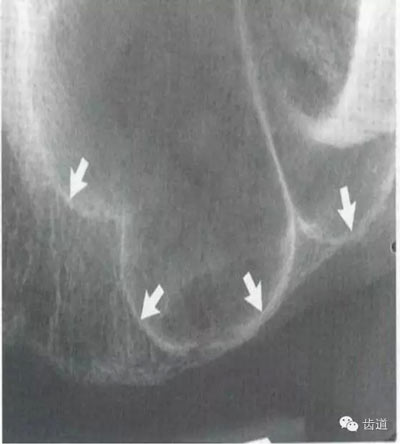

位于磨牙牙根尖下方,呈寬約為0.4cm凹面向下邊緣整齊的帶狀密度低的影像,其兩側(cè)有密度高的線條狀影像,為下頜管骨密質(zhì)